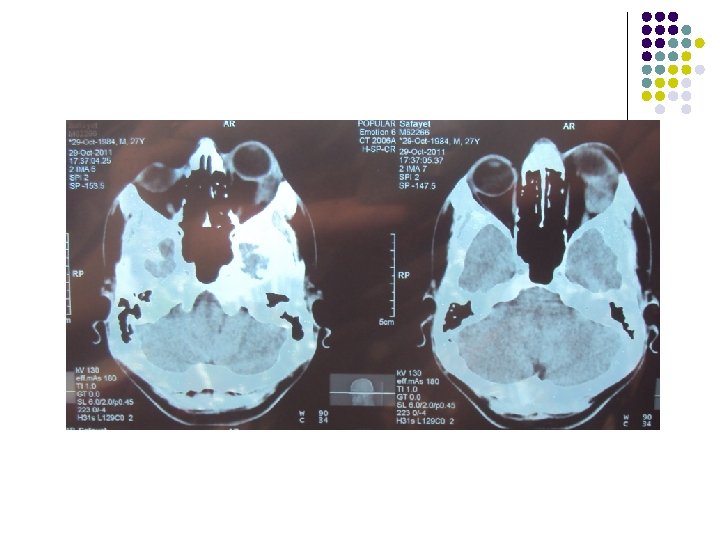

CT Scan of Brain

Clinical Diagnosis Retrobulbar solid tumour on left orbit